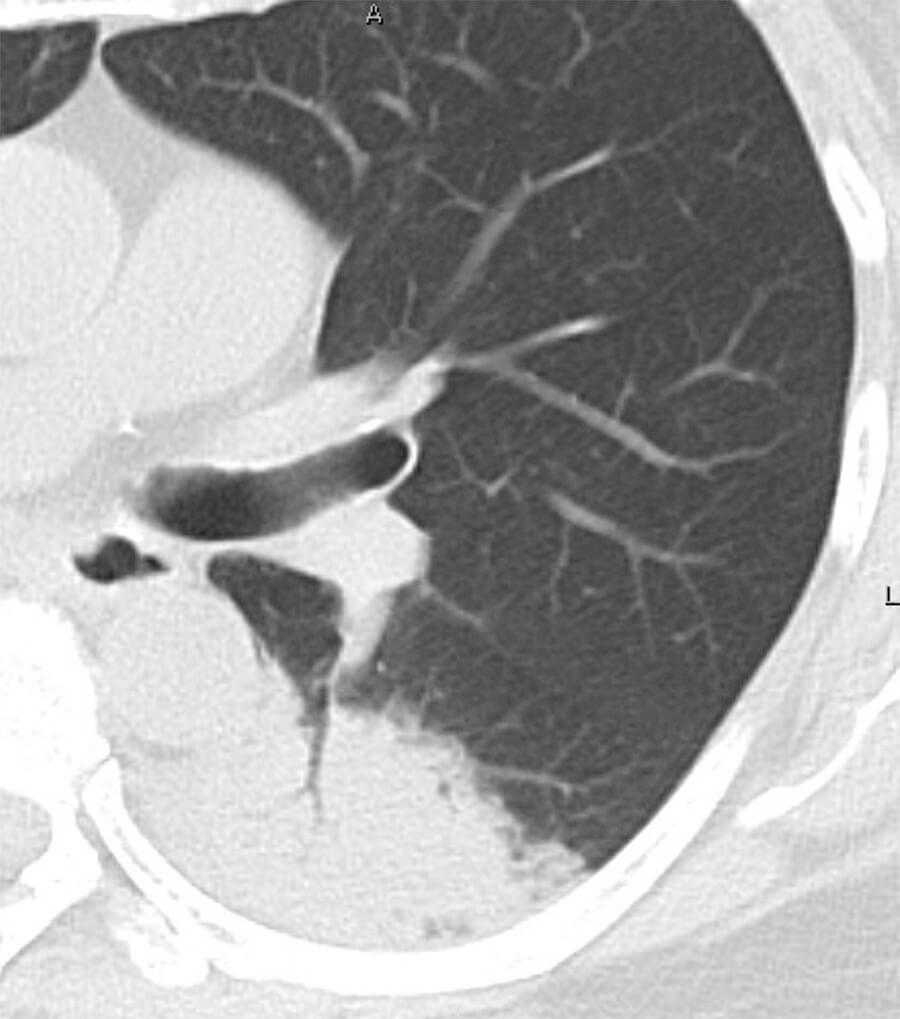

間質性肺炎

肺の間質(構造の支えとなる組織)が炎症や線維化を起こしている状態で、すりガラス陰影や網状影、蜂巣状変化などがCTで確認されます。息切れや乾いた咳が長く続くのが特徴で、進行すると呼吸不全に至ります。初期においては、健診などで行われる胸部単純写真(X線写真)では見逃されることも多いため、症状や経過をみて、特に長引く咳や労作時の息切れがある場合には、早期のCT検査が推奨されます。

当院では、複数の呼吸器専門医及び放射線科診断専門医がカンファレンスを行い、間質性肺炎の精密検査・治療が必要と判断された場合は、速やかに連携高次医療機関へご紹介いたします。